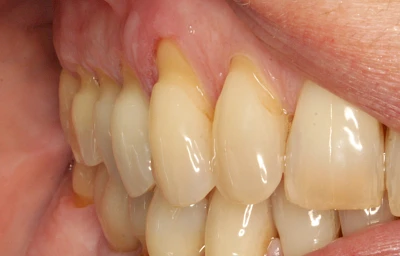

- Knirschen bzw. Pressen und ungünstige Putztechnik (Druck): keilförmige Defekte

Keilförmiger Defekt

Eine Sonderform sind sogenannte keilförmige Defekte im Bereich der Zahnhälse. Hier geht man davon aus, dass Knirschen und Pressen in Kombination mit falschen Putzgewohnheiten (zu hoher Putzdruck, Verwendung von Zahnpasta mit hohen Abrasionswerten) eine Rolle spielen.